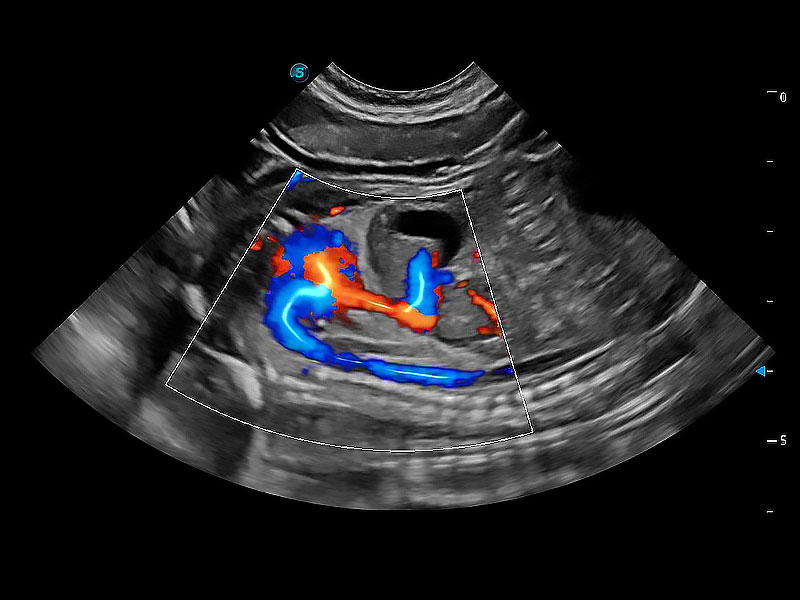

(犬)胎儿主动脉弓立体血流

(犬)胎儿四腔心